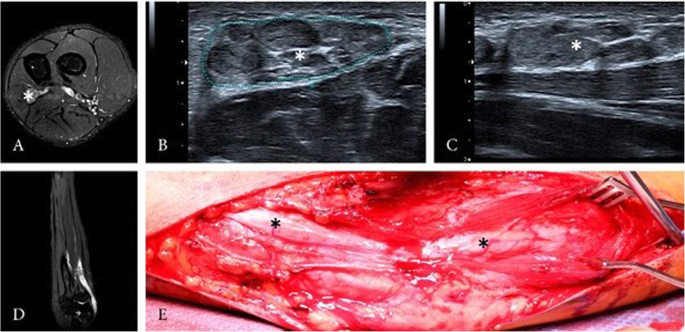

A 56-year-old male patient with typical clinical and electroneurographic findings of carpal-tunnel-syndrome caused by an intraneural PN of the right median nerve presented to our neurosurgical department. The patient complaint about a progressive hypaesthesia and paresis of the hand and underwent 4 surgeries over a period of 30 years without long term benefit because of suspected carpal-tunnel-syndrome. HRNS and magnetic resonance imaging (MRI) of the right-hand depicted an intraneural PN of the median nerve (Fig. 2). Follow-up examination 27 months after surgery showed an improvement in motor function undergoing physiotherapy, but no change of the sensory deficits. HRNS revealed stable intraneural PN.

Case 2

A 16-year-old left-handed male patient presented with an intraneural PN of the left ulnar nerve. Symptoms lasted over 2 years, showing a progressive atrophy of the intrinsic muscles of the left hand without any sensory deficit. Electrophysiological testing revealed an impairment of the left ulnar nerve, HRNS and MRI of the left arm showed intraneural PN of the ulnar nerve with a length of about 15 cm reaching from the middle of the upper arm to the middle of the forearm (Fig. 3). Despite the atrophy of the intrinsic muscles of the hand, follow-up examination 24 months after surgery showed a stable state of the PN on HRNS, without any sensory deficit. The functionality of the hand improved under consequent physiotherapy.